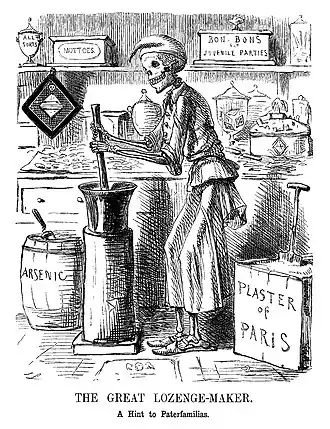

Prescientific forms of medicine, now known as traditional medicine or folk medicine, remain commonly used in the absence of scientific medicine and are thus called alternative medicine. Alternative treatments outside of scientific medicine with ethical, safety and efficacy concerns are termed quackery. (Full article...)

Selected image –

General images –